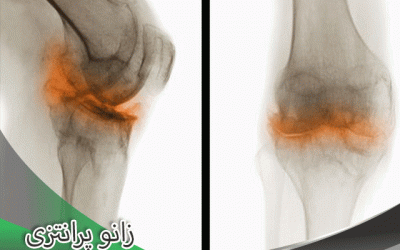

تشخیص و درمان پای پرانتزی

زانوی پرانتزی از جمله مشکلاتی است که علاوه بر اینکه احتمالا در ظاهر فرد موجب بروز مشکل می شود و از اعتماد به نفس افراد می کاهد از سوی دیگر نیز بر ساختمان بدن و استخوان های فرد تاثیرات منفی گذاشته و...